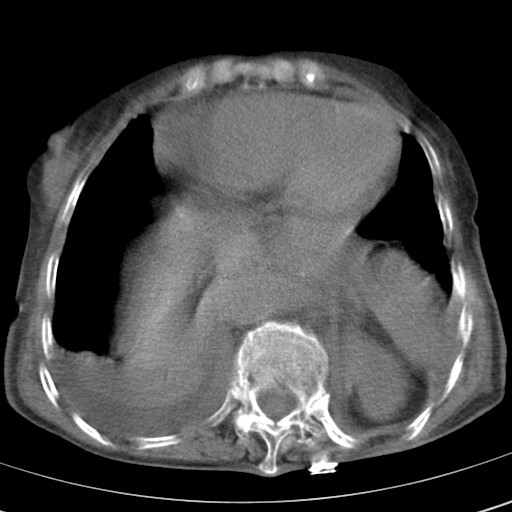

女,93岁,摔伤后检查。

食管裂孔疝

创伤性湿肺,双侧胸腔积液。可能有食管裂孔疝,进一步检查。骨折有无根据自己的机器及片子再仔细看吧。

右侧锁骨\\肩胛骨骨折、右侧湿肺,心功能不全伴双侧胸腔积液,右下肺膨胀不全,左膈破裂或食管裂孔疝,冠脉钙化,心包少量积液,请上传骨窗.

右肺炎症,心功能不全伴双侧胸腔积液,右下肺膨胀不全,食管裂孔疝,冠脉钙化,心包少量积液,左侧肋骨骨折,右肩甲骨粉碎性骨折。93岁,高寿哇!

右肺炎症,心功能不全伴双侧胸腔积液,右下肺膨胀不全,食管裂孔疝,冠脉钙化,心包少量积液,左侧肋骨骨折,右肩甲骨粉碎性骨折。